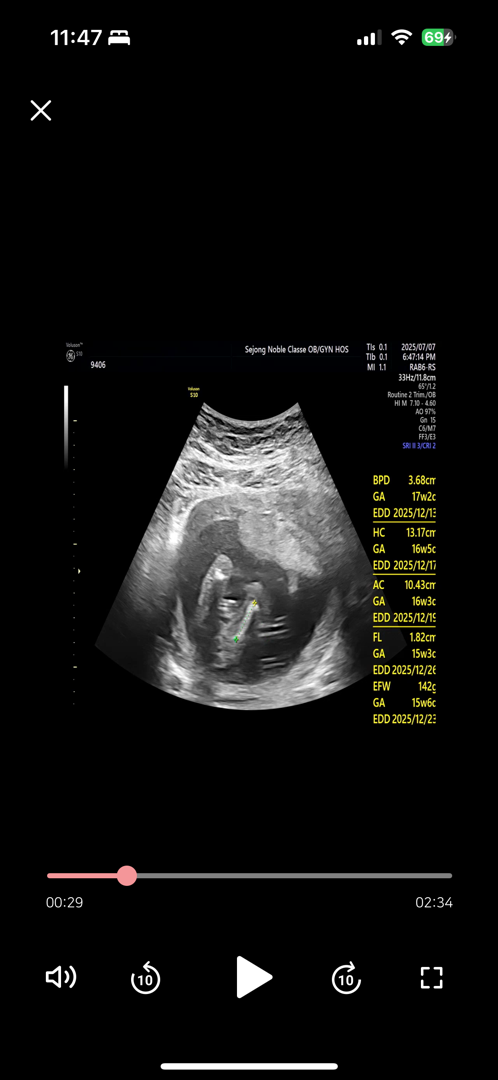

16주1일 춈파 입니다 성별 봐쥬세요!!! 똥꼬 쪽 다리 밑에서 봐주시는 춈파입니다!!